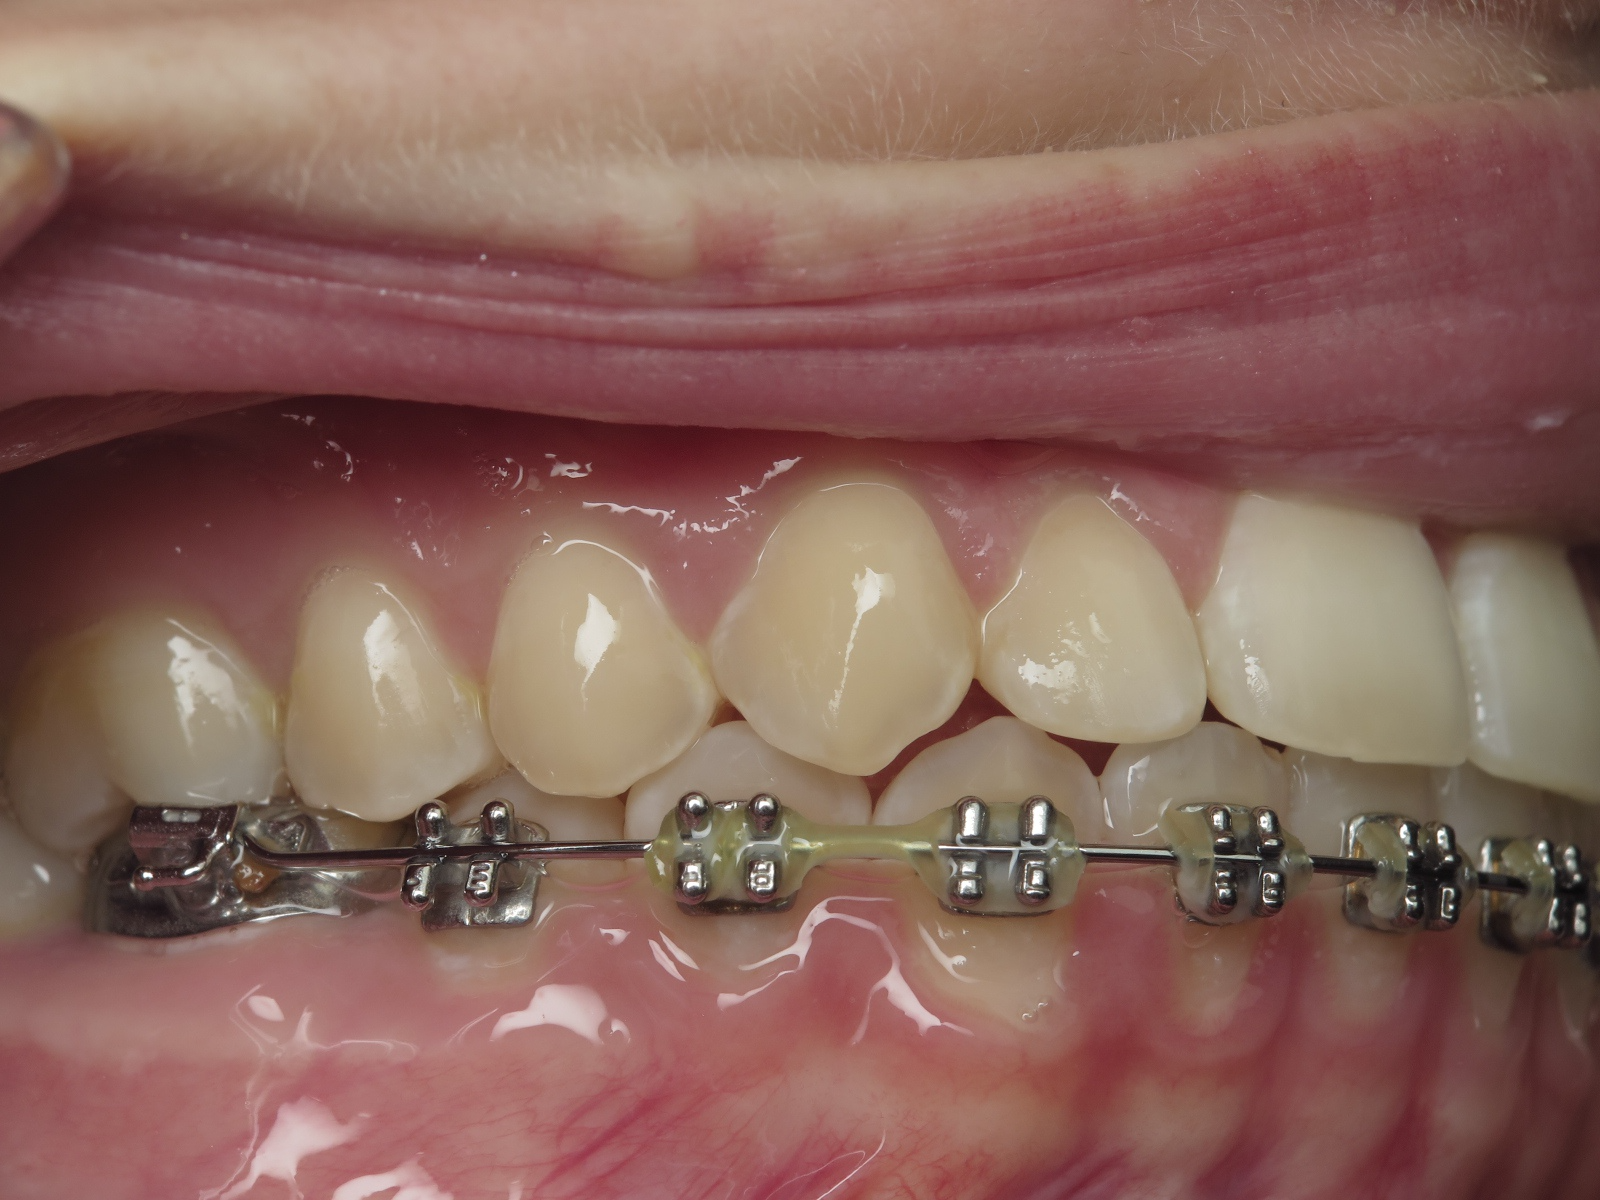

appareillage multibagues traitement en cours

bilan début et en cours de traitement